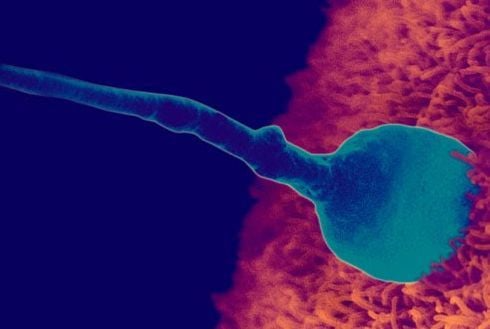

Quá trình thụ thai chỉ có thể được xảy ra khi có đủ hai yếu tố quan trọng là tinh trùng và trứng.

Quá trình thụ thai chỉ có thể được xảy ra khi có đủ hai yếu tố quan trọng là tinh trùng và trứng.

Chỉ có một tinh trùng khỏe mạnh nhất mới có thể vào trong âm đạo của phụ nữ